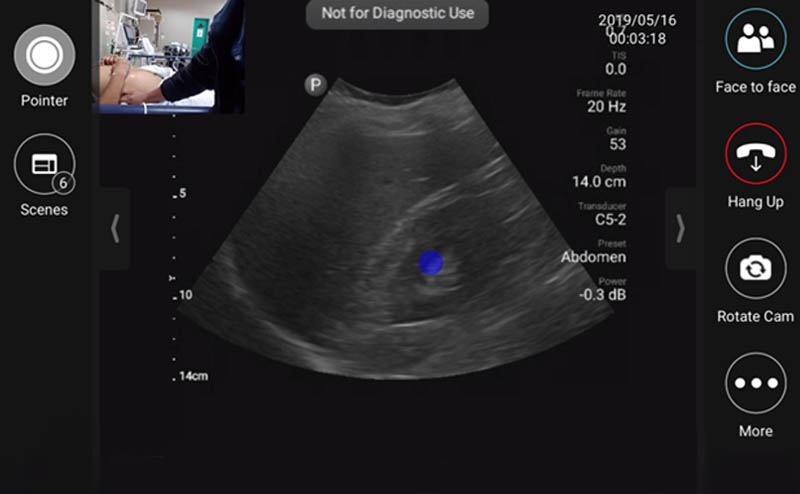

EUS_10-2024-Article1-1.jpgFigure 1. Tele-ultrasound platform as visualized by remote user providing diagnostic/procedural assistance

During the initial months of the fellowship, onsite support during the fellow’s scanning shifts was provided by volunteer visiting instructors from the US. Following this initial period, visiting instructors were not always present in Lima, however fellows could utilize the built-in tele-ultrasound software on the handheld ultrasound device to contact a pool of on-call physicians during their required ultrasound scanning shifts. The inaugural year of the fellowship we primarily relied on tele-ultrasound to provide live support during the fellow’s self-directed scanning shifts whenever questions arose.

In 2020, year three of the fellowship, we were forced to adapt to strict travel restrictions enforced due to the COVID-19 pandemic. We suddenly were forced to rely primarily on tele-ultrasound to provide ongoing teaching and support. We shifted from utilizing tele-ultrasound on an as needed basis to scheduling tele-ultrasound scanning shifts accompanied by a senior ultrasound fellowship trained instructor located either in the US or Peru. An added benefit of having graduated five classes of fellows to date is that we can now rely on former fellowship graduates to host tele-ultrasound sessions with the new class of fellows.